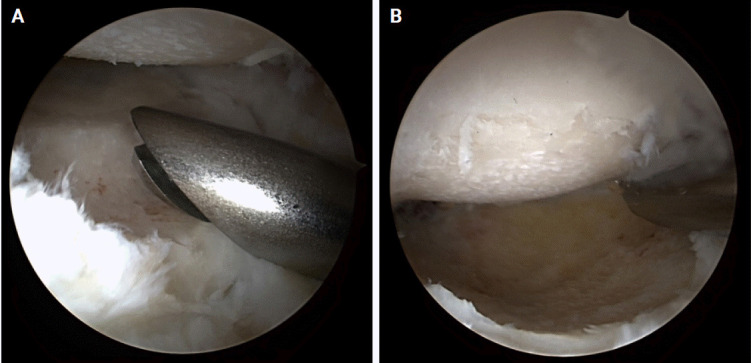

Background: Radiocapitellar arthritis can cause pain, loss of motion, and impaired elbow function. Current surgical treatment options are limited. We have developed an original and simple surgical technique to address this, called arthroscopic matched osteoplasty of the radial head (AMOR). In AMOR, the radial head is partially resected and recontoured to match the capitellum and decompress the degenerate radiocapitellar articulation while preserving the ulnohumeral articulation where the cartilage is usually well preserved.

Conclusions: AMOR is a safe treatment option for painful radiocapitellar osteoarthritis and can be incorporated as an "add-on" procedure by surgeons performing elbow osteocapsular arthroplasty in cases with a positive grip and grind test and radiographic evidence of radiocapitellar OA. Level of evidence: IV.